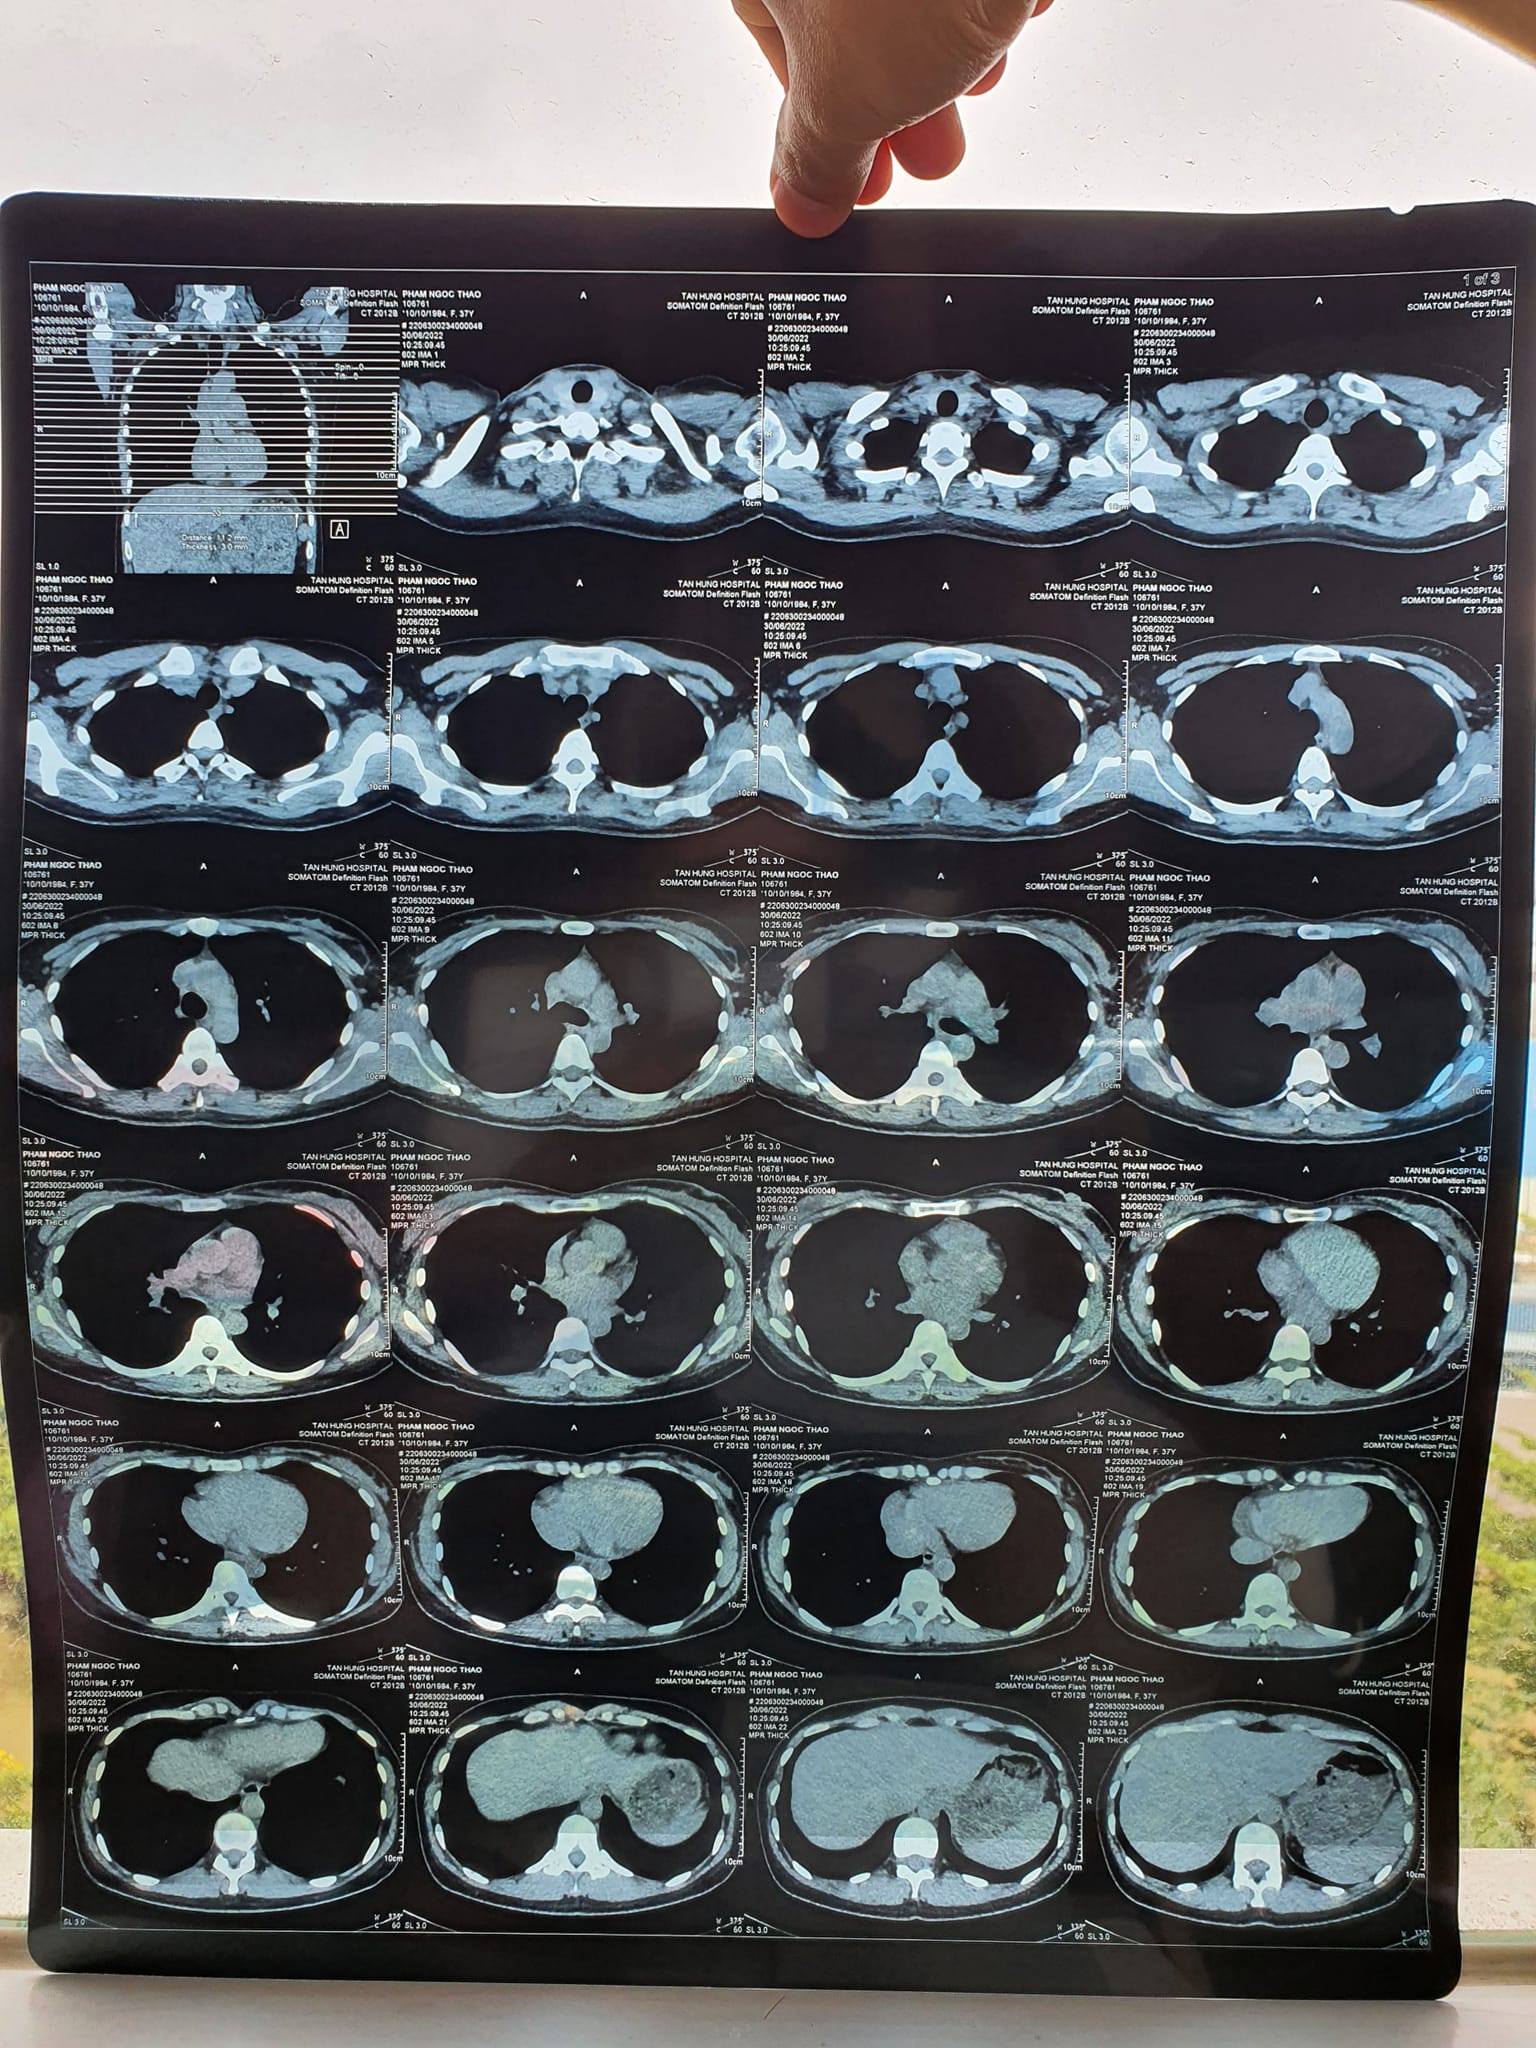

“Thầy còn nhớ ca bệnh năm ngoái chữa viêm phổi cho vợ em không? Thầy chữa 2 tuần liên tục đỡ rồi vợ em về không phải uống thuốc và sinh được bé nhà em. Giờ có biểu hiện lại vợ em đi khám thì có khối u trong phổi. Nên em không thực hiện mổ theo lời bác sĩ nữa mà em muốn nhờ thầy chữa tiếp ạ. Chữa bằng Năng lượng sinh học 2 tháng sau thì chụp X quang lại và CT lại cho kết quả. Chụp X quang thẳng không thấy tổn thương nữa, xong bác sỹ nói chụp nghiêng cho rõ hơn cũng không còn tổn thương. Rồi em yêu cầu chụp CT cho chắc thì kết quả là không thấy khối u nữa ạ. Dạ em cảm ơn thầy nhiều nhiều nhé”

Kết quả X quang và CT sau khi chăm sóc sức khỏe bằng Năng lượng sinh học vào ngày 30/6/2022